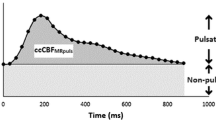

The CBF was calculated by summarizing the flows in the carotid and vertebral arteries. The internal jugular vein flows were evaluated in the same manner and summarized providing the internal jugular venous flow. The internal jugular vein flow ratio, i.e., the part of the cerebral venous outflow flowing through the internal jugular veins, was calculated by dividing internal jugular venous flow with CBF. The venous pulsatile index was used to correlate venous pulsatility to ICP. Venous pulsatile index is calculated by the formula 100 × (Fmax − Fmin)/Fmax, where Fmax is the maximum flow and Fmin is the minimum flow over the cardiac cycle [15] (Fig. 2).

The flow rates over one cardiac cycle in one individual. IJVflow, the combined flow in the internal jugular veins, Fmax, maximum flow, Fmin minimum flow. The pulsatile component of internal jugular vein flow is represented by the gray area; the non-pulsatile component of internal jugular vein flow is represented by the white area

A rise in mean ICP lowers the pulsatile component of the venous outflow, and in order to have an unchanged venous outflow the non-pulsatile component must increase (Fig. 2). We did not find a correlation between increasing mean ICP and increased Fmin, although a correlation between minimal flow velocity and ICP has previously been demonstrated using TCD [24]. However, the Fmin is an absolute value and thereby highly dependent on the ratio of the cerebral venous outflow flowing through the internal jugular veins. With just small variations in the Fmin together with the high level of inter-individual variation regarding the internal jugular venous ratio of cerebral venous outflow, such a correlation could easily be missed.